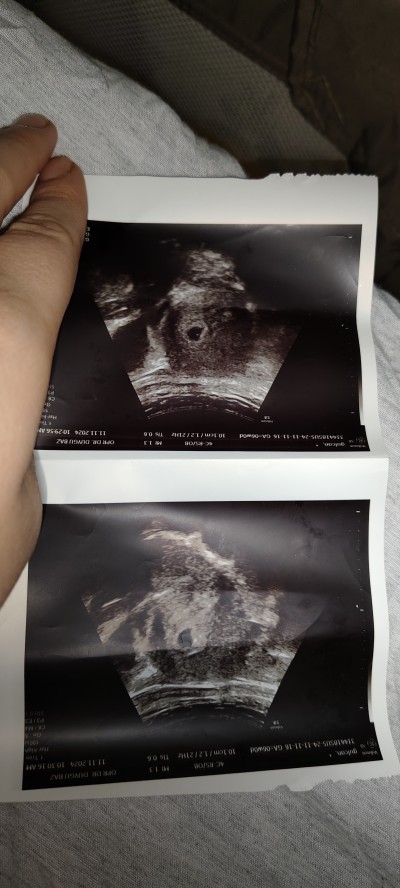

Bebek gelmemiş keseye dedi ama oradaki nokta nedir acaba

Gebelik haftası 6

Kuzum daha çok küçük ya ondan görünmüyordur nokta yolk sac kesesi olabilir çok erken ogrenmissin büyük ihtimalle yolk sac kesesi varsa bebek de oluyor hiç endiselenme

Görürsün muhtemelen bende altı artı dörtte görmüştüm bebeğimi